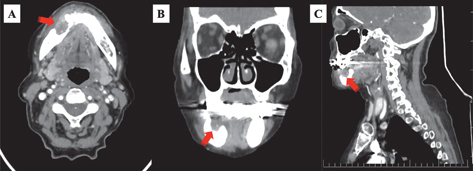

Fig 3

Figure 3. Computed tomography. Osteoradionecrosis in the anterior of the right mandible corpus is demonstrated as a lytic, slightly expansile, and defective region (red arrows). A: axial; B: coronal; C: sagittal.